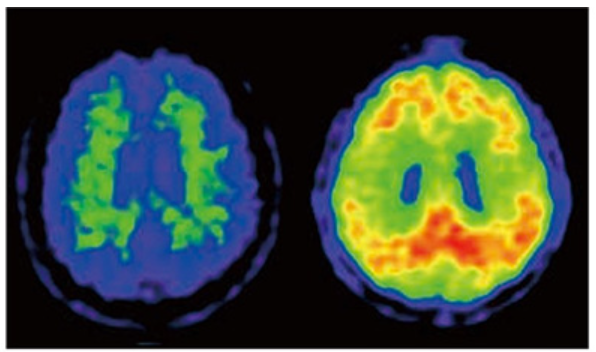

여기서 MRI, PET, SPECT 검사가 매우 유용합니다. 발병 전 알츠하이머병의 단계는 MCI 이전 단계에서 증상이 전혀 없습니다. 이 단계에서는 MRI와 SPECT 검사에서 이상을 찾는 것은 어렵지만, 아밀로이드 PET와 수액 검사가 도움이 됩니다.수액얼음검사는요추사이에 바늘을 찌르고 수액을 빼내기 때문에 침습적인 검사라고 할 수 있습니다.

한편, PET 검사는 정맥 주사 후 머리를 촬영할 뿐이므로 비침습적 검사라고 할 수 있습니다. 이 PET 검사는 현시점에서는, 아직 임상 연구로서 검사가 행해지고 있지만, 아밀로이드 PET라고 하는 특수한 검사가 있습니다. 이것은 뇌를 해부하지 않고 PET 검사로 뇌에 아밀로이드가 쌓여 있는지 여부를 진단 할 수있는 방법입니다. 아밀로이드는 알츠하이머병의 증상이 나오기 20~30년 전부터 축적하기 시작한다고 하며, 아밀로이드 PET는 큰 기대를 갖고 있습니다.